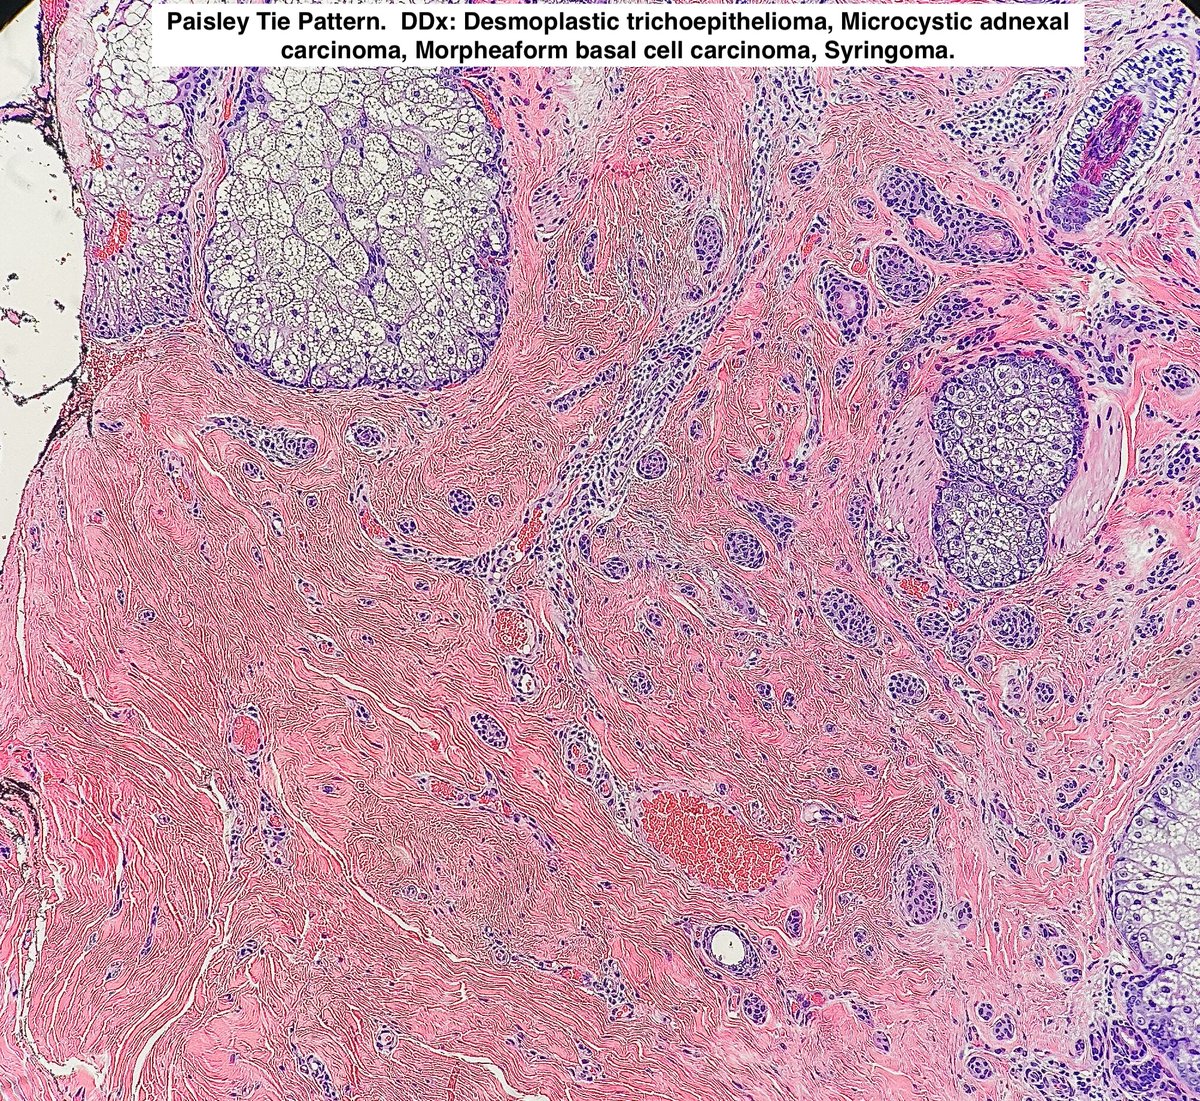

👋 Hello I often occur on the face of elderly Caucasian patients I am a Paisley Tie Ddx 🤵 I often am found deep in the skin and may have perineural invasion Who am I? 🤔 #skin #dermpath #skintumors #adnexaltumors #pathx #dermatology #pathology